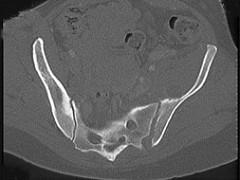

男,56岁,右髋部疼痛,结合图像,最可能的诊断是 ( )A、骨转移瘤B、类风湿关节炎C、骶髂关节结核D、强直性脊柱炎E、骶髂关节炎

问题 男,56岁,右髋部疼痛,结合图像,最可能的诊断是 ( )

选项 A、骨转移瘤 B、类风湿关节炎 C、骶髂关节结核 D、强直性脊柱炎 E、骶髂关节炎

答案 E